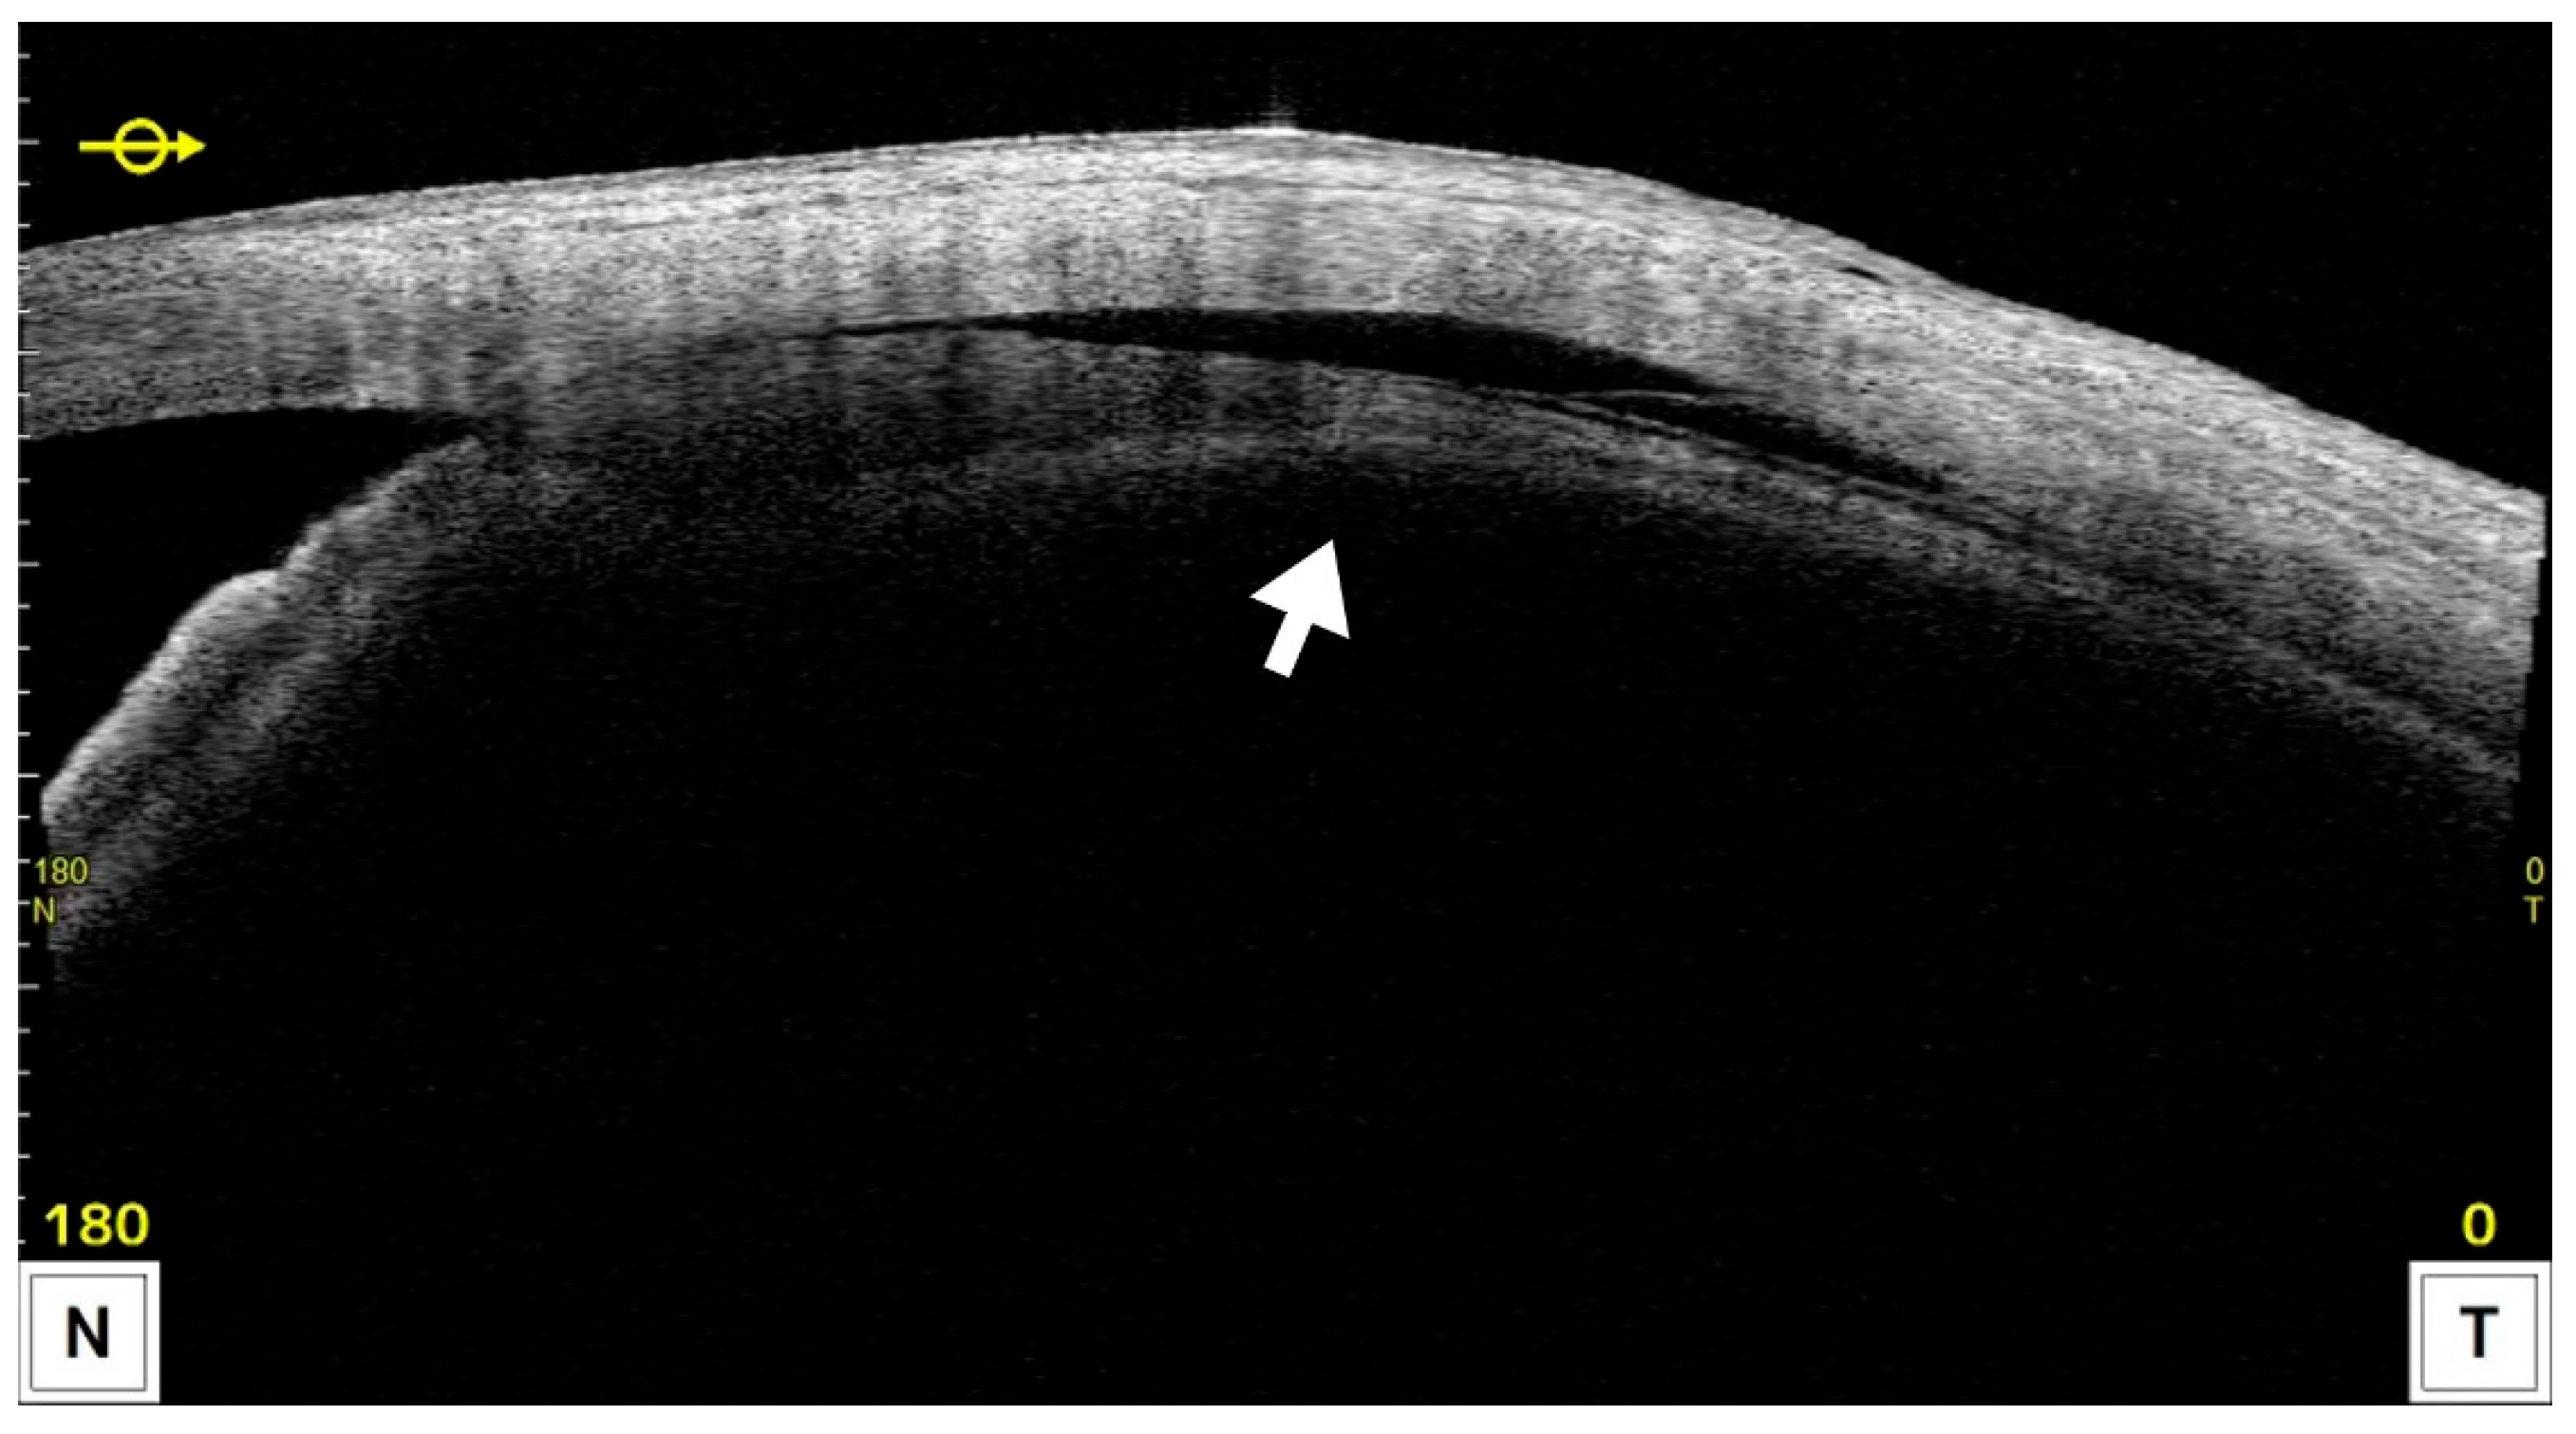

- Chansangpetch, S.; Taechajongjintana, N.; Ratanawongphaibul, K.; Itthipanichpong, R.; Manassakarn, A.; Tantiseve, V.; Rojanapongpun, P.; Lin, S.C. Ciliochoroidal effusion and its association with the outcomes of micropulse transscleral laser therapy in glaucoma patients: A pilot study. Sci. Rep. 2022, 12, 16403. [Google Scholar] [CrossRef] [PubMed]